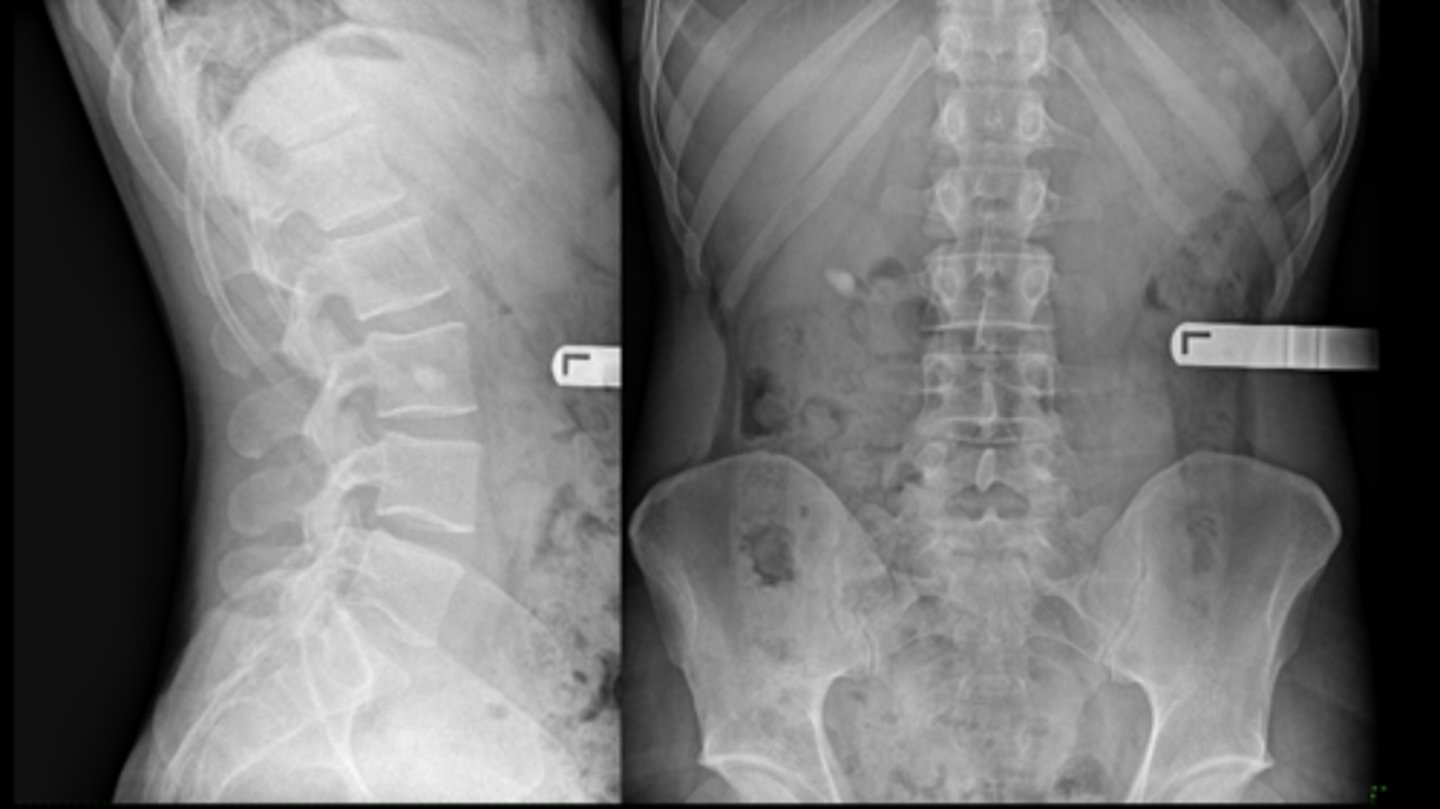

- Bone island

- Kidney stone*

22 y.o. male with L/S pain, post motor vehicle accident

- Differential diagnosis?

<p>22 y.o. male with L/S pain, post motor vehicle accident</p><p>- Differential diagnosis?</p>